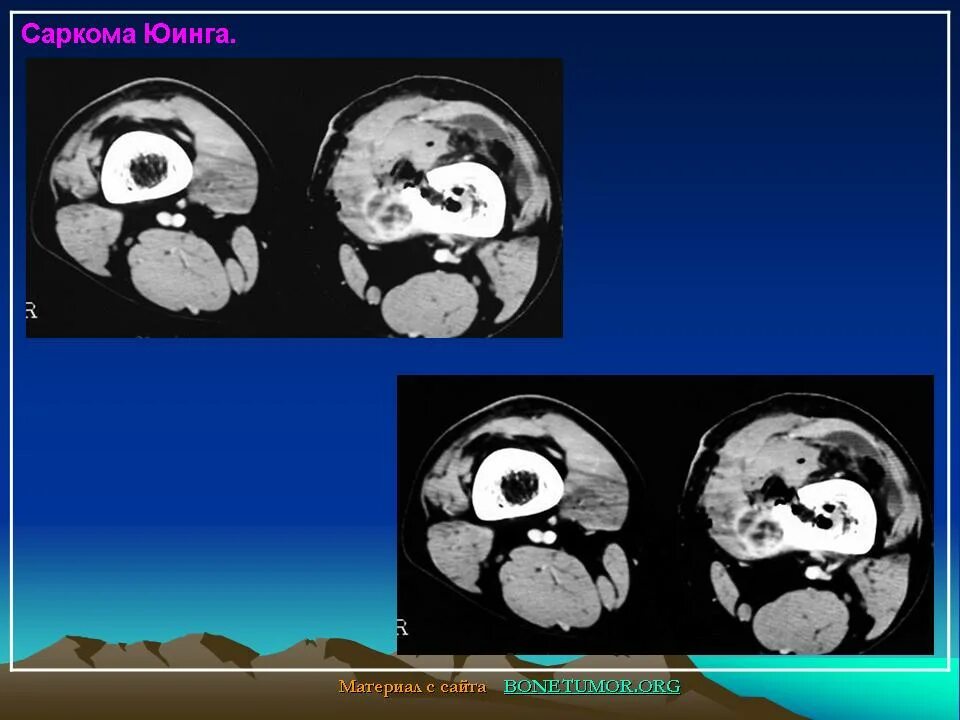

Саркома мрт